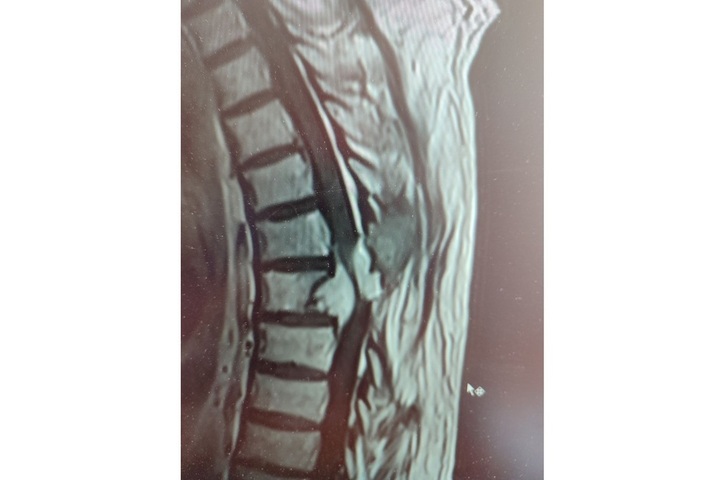

Жителю Балаково провели сложнейшую операцию по  удалению опухоли грудного отдела позвоночника, сдавившей спинной мозг. Об  этом рассказали в  Telegram-канале ГУЗ СО  «Балаковская городская клиническая больница». Медики пишут об  этом случае следующее:

«В  2014 году пациент уже жаловался на  слабость в  ногах. При обследовании у  него выявили опухоль на  уровне седьмого грудного позвонка. Операцию выполнил Михаил Дёрин. После нее мужчина вернулся к  обычной жизни и  семь лет не  вспоминал о  недуге.

С  2021 года пациент вновь стал отмечать слабость в  ногах, но  на  этот раз симптом проигнорировал. К  нейрохирургам он  обратился лишь осенью 2023 года. У  него повторно нашли растущую опухоль, которая на  этот раз уже со  всех сторон сдавливала спинной мозг. Требовалось вмешательство специалистов федерального масштаба.

В  мае, когда мужчину вновь госпитализировали в  балаковскую больницу, он  уже практически не  мог ходить самостоятельно. Нейрохирург Александр Майоров ещё раз изучил результаты исследований и  всё-таки согласился помочь. В  итоге 17  мая 2024 года, в  ходе трехчасовой операции, пациенту выполнено удаление большей части опухоли из  позвонка с  полным освобождением спинного мозга. Уже на  следующий день после операции он  почувствовал нарастание силы в  ногах.